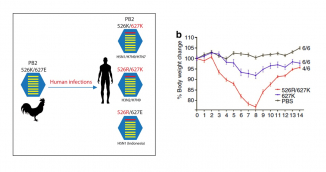

Host barriers block cross species transmission and replication of animal viruses in humans. Such host restriction mechanism limits the transmissibility and the ability of the avian virus to cause mammal and human infections. However, research team led by Dr. Honglin Chen, Associate Professor, and Professor Kwok-yung Yuen, Henry Fok Professor in Infectious Diseases, Chair Professor of Infectious Diseases from the Department of Microbiology, Li Ka Shing Faculty of Medicine, and State Key Laboratory for Emerging Infectious Diseases, the University of Hong Kong, found that avian influenza viruses may gain the ability to replicate in mammal and human cells through various adaptation changes in one of the viral replication complex subunits called the PB2, causing infections and diseases in humans. The discovery has been published recently in Nature Communications, in which team members Drs. Wenjun Song and Pui Wang are co-first authors.

In a recent study reported in the Nature Communications, a research team led by Dr. Honglin Chen, Associate Professor, and Professor Kwok-yung Yuen, Henry Fok Professor in Infectious Diseases, Chair Professor of Infectious Diseases from the Department of Microbiology, Li Ka Shing Faculty of Medicine, and State Key Laboratory for Emerging Infectious Diseases, the University of Hong Kong, found that avian influenza A H5N1 and H7N9, and seasonal H3N2 viruses may gain the ability to replicate in mammal and human cells through various adaptation changes in the viral replication enzyme complex called the PB2 subunit. They found that H7N9 avian influenza A virus is able to utilize multiple adaptive strategies to replicate in human cells, which may explain why H7N9 is distinct in causing human infections; This study identified a novel adaption marker, PB2-526R among some H7N9 viruses and almost exclusively among all H5N1 human cases from Indonesia. It has been a puzzle why there is no known PB2 adaptation marker in the H5N1 virus from Indonesia human cases and the finding from HKU nicely explained how this Indonesian subclade of avian H5N1 virus may have adapted for human infections. This study also found PB2-526R is able to enhance replication and pathogenicity of other types of PB2 adaptations, such as previously known PB2-627K, in H7N9 and H3N2 viruses. Since the human pandemic H3N2 virus emerged in 1968, it has gained an additional PB2-526R adaptation marker since 1970s and the PB2-526R-627K virus replicates better than the solely PB2-627K virus. It is likely that the impression of more severe disease burden caused by H3N2 than that of H1N1 may be partly attributed to the better replication ability of PB2-526R-627K virus. These findings by HKU provided new insight for the understanding of cross species transmission and replication in human cells by avian influenza viruses. The study provides a new genetic marker for the surveillance of avian influenza A virus with potential for human infection.